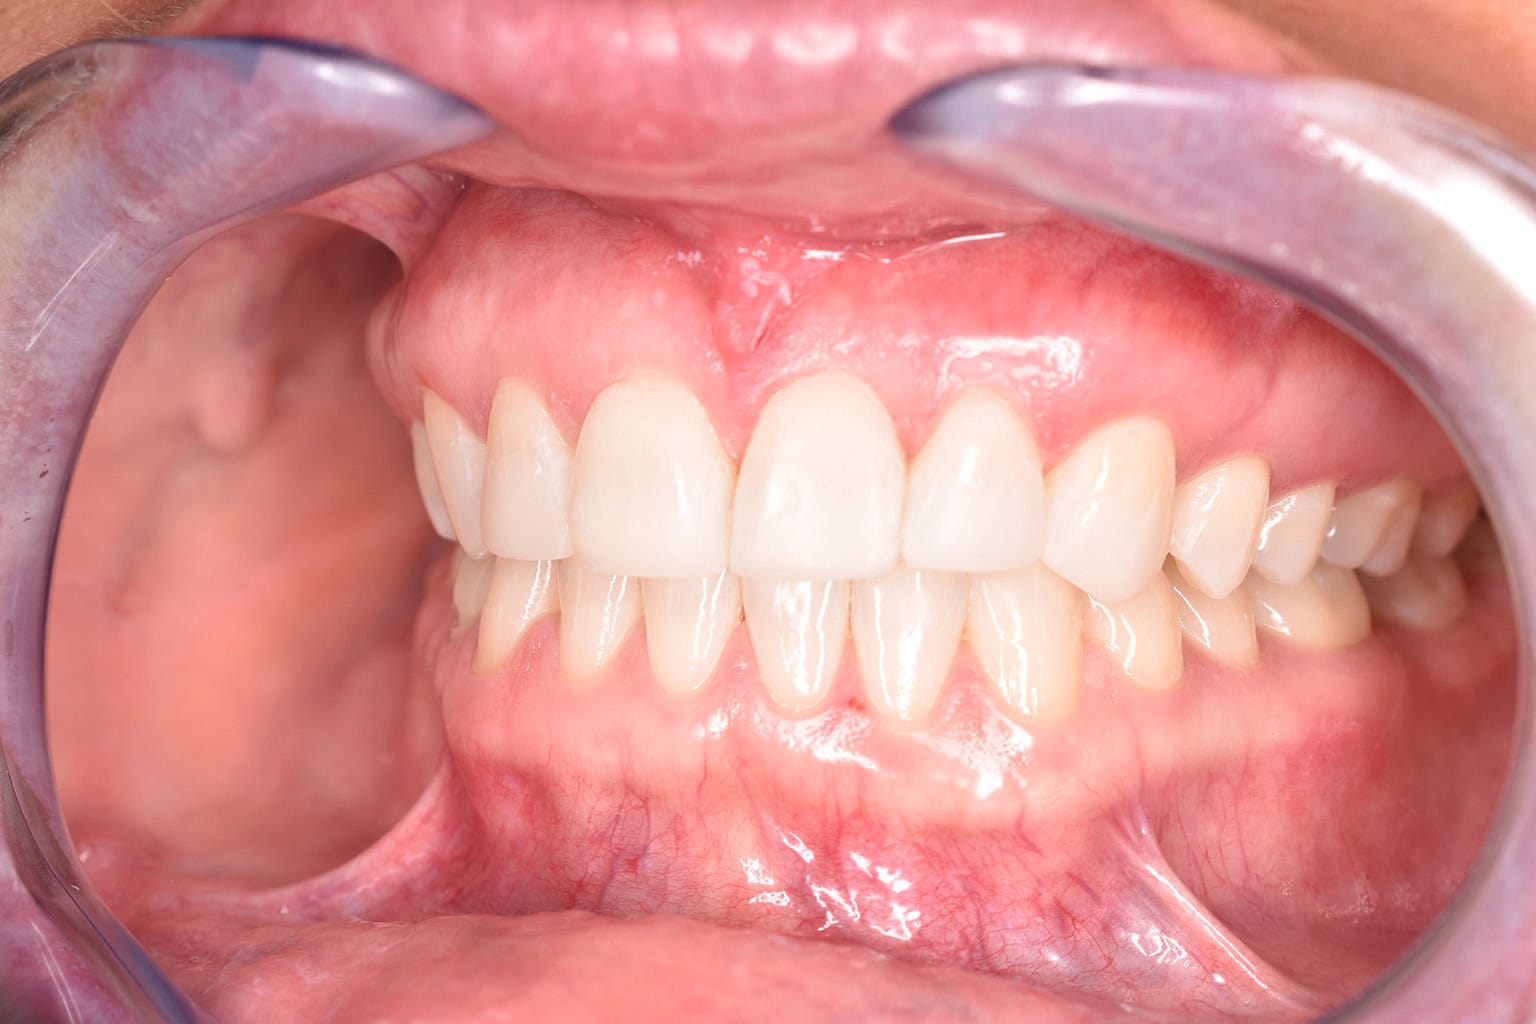

Vorher-Nachher-Ergebnisse

Echte Ergebnisse. Echte Menschen.

Jede Behandlung bei TIEFBLAU Kieferorthopädie ist so individuell wie der Mensch dahinter. In unserer Vorher-Nachher-Galerie zeigen wir Ihnen echte Behandlungsergebnisse aus unserer Praxis in der Kölner Südstadt: Schonend erzielt, präzise geplant und mit dem Anspruch, den wir seit über 40 Jahren an jede Behandlung stellen.

Die Bilder geben Ihnen einen Eindruck davon, was moderne Kieferorthopädie leisten kann, ob bei Kindern, Jugendlichen oder Erwachsenen.

Der sichtbare Unterschied

Dokumentiert. Überzeugend. Nachhaltig.